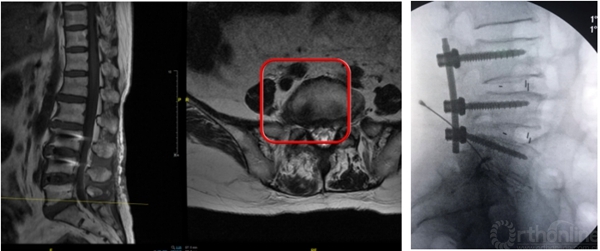

有些病例椎板间入路手术更加简单,尤其对于L5/S1脱垂病例

L5/S1钙化型突出(骺环离断症),椎板间减压更加充分彻底,需配备磨钻动力系统